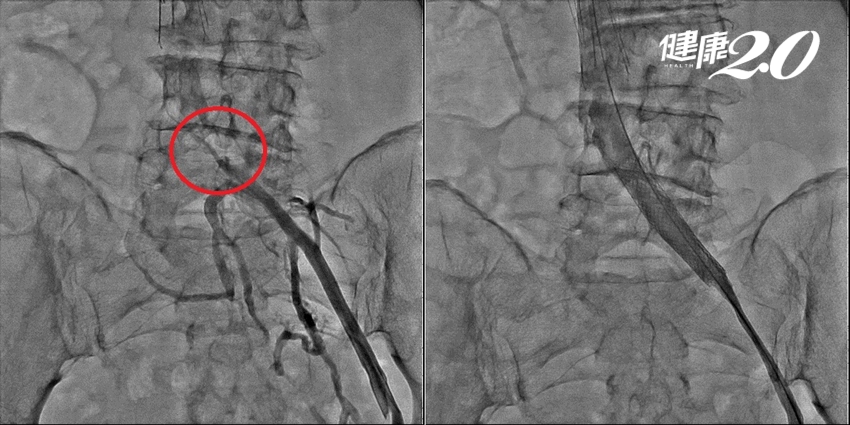

▲ 婦人的左髂總靜脈被壓扁、只剩縫隙(圖左紅框處),清除血栓後以支架順利撐開(圖右)。

為了防止血塊漂流回心臟、引發肺動脈栓塞恐危及生命,張耿豪先在患者的靜脈裡放置「過濾網」,再進行導管血栓清除術,並置放支架撐開被壓扁的左髂總靜脈。術後隔天,婦人左腳腫脹已消失,再追蹤靜脈照影,確認已清除膝蓋以上90%的血栓。